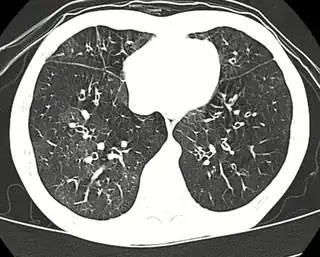

![]() Tomografía computada de alta resolución mostrando una bronquiolitis obliterante con atenuación en mosaico, broquiectasias, atrapamiento aéreo y engrosamiento bronquial[2] | ||

Las causas incluyen respirar gases tóxicos, infecciones respiratorias, trastornos del tejido conectivo o complicaciones después de un trasplante de médula ósea o de corazón y pulmón.[1] Es posible que los síntomas no se presenten hasta dos a ocho semanas después de la exposición tóxica o la infección.[1] El mecanismo subyacente involucra inflamación que da como resultado la formación de tejido cicatricial.[1] El diagnóstico se realiza mediante tomografía computarizada, pruebas de función pulmonar o biopsia pulmonar.[1] Las radiografías de tórax suelen ser normales.[3]